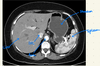

label the arrows on this abdominal CT